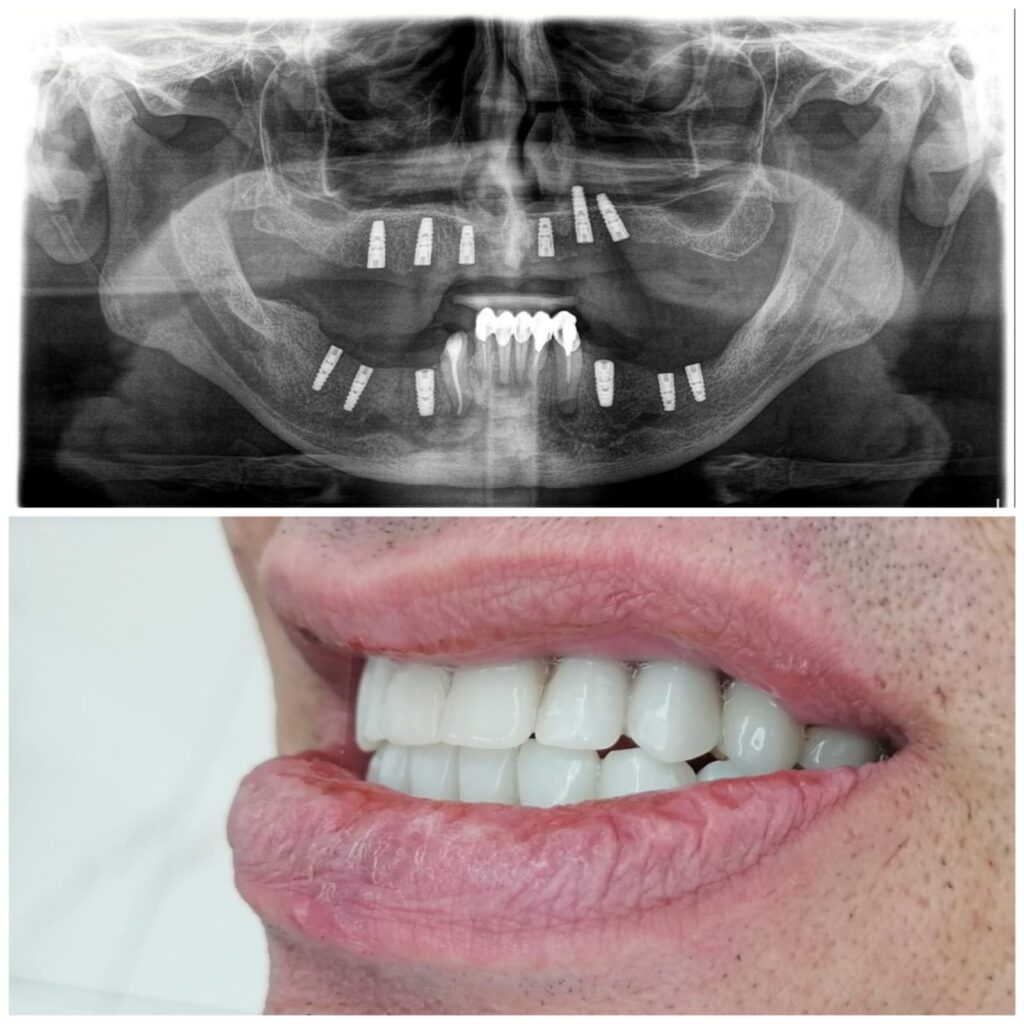

يترأس مراكزنا فريق مختار بعناية من خبراء زراعة الأسنان. وبعد عملية الزرع يتم تركيب التيجان والجسور ، والتي يتم تصميمها بأقصى قدر من الدقة والجمالية لمنحك الابتسامة المثالية.

لقد حققنا نجاحاً في مجالنا ، حيث قمنا بعمل الآلاف من عمليات الزرع للأشخاص في جميع أنحاء العالم بمعدل نجاح بلغ 96٪.

يتم تخطيط وتنفيذ إجراء زراعة الأسنان بعناية لضمان أن ترميم الأسنان يبدو طبيعيًا في الشكل واللون والمكان. نعطي الأولوية لراحة مرضانا بالإضافة إلى الجماليات. وهذا يتطلب مزيجًا مثاليًا من العبقرية الفنية والجراحية. لذلك ، يتم تنفيذ جميع حالات الزرع لدينا من قبل فريق من أطباء الأسنان التجميليين وأخصائي زراعة الأسنان.